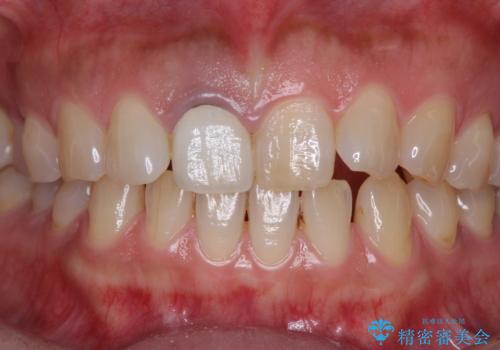

- セラミッククラウンが白すぎる前歯と、放置している奥歯を気にして来院された患者様です。

前歯のセラミッククラウンは将来ホワイトニングをするつもりで白くしたものの、それほど白くならず、ホワイトニングも面倒くさいとのことで白すぎる印象となっていました。

前歯のセラミッククラウンは周りの歯と調和させるためにオーダーメイドタイプのものをおすすめしましたが、元が白すぎていたため、概ね色合いが合えば大丈夫であるとのことで、既製パターンの色調で仕上げました。